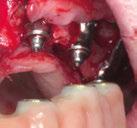

Ejecución técnica quirúrgica mediante férula guiada Bajo anestesia infiltrativa realizamos extracciones atraumáticas de todas las piezas a excepción de los dientes que actúan como anclaje o pilares para la fijación de la férula quirúrgica (Figuras 20 y 21). Seguidamente insertamos la férula comprobando una buena adaptabilidad y estabilidad

Figura Figura en posición ideal. Figura Figura

34 CIENCIA Y CLÍNICA. Caso clínico Gaceta Dental · N o 366 | Mayo 2024

Figura

de dientes estratégicos para fijar la férula quirúrgica.

Figura 23. Férula quirúrgica inferior. Figura 24. Fresado guiado con férula y cucharilla. Figura 20. Extracciones dentales. 21. Conservación Figura 22. Férula quirúrgica superior. Figura 25. Inserción de implante RSX de Bego a través de férula quirúrgica. Figura 27. Conexión de pilar angulado multiplus sobre implante. Figura 26. Implante insertado en lecho a través de férula quirúrgica. Figura 28. Muestra del perfecto paralelismo tras la colocación de pilares angulados multiplus. Figura 29. ScanBody sobre pilares transepiteliales.

(Figuras 22 y 23). Se realiza fresado transgingival mínimamente invasivo y guiado hasta la inserción de los implantes, siguiendo el protocolo preestablecido e indicado (Figuras 24 a 26).

Durante la colocación de los implantes comprobamos una inserción con torque superior a 35 N/cm2

Retiramos la férula y comprobamos una correcta estabilidad primaria mediante mediación de valores

ISQ favorables en la mayoría de los implantes. Seguidamente se extraen los dientes remanentes que han actuado de medio retentivo para la férula quirúrgica.

Dentro de la fase quirúrgica propiamente dicha, una vez terminada la inserción de los implantes y

comprobada su estabilidad primaria, colocamos pilares transepiteliales

Multiplus para registrar una impresión digital mediante escaneado sobre ellos (Figuras 27 a 29)